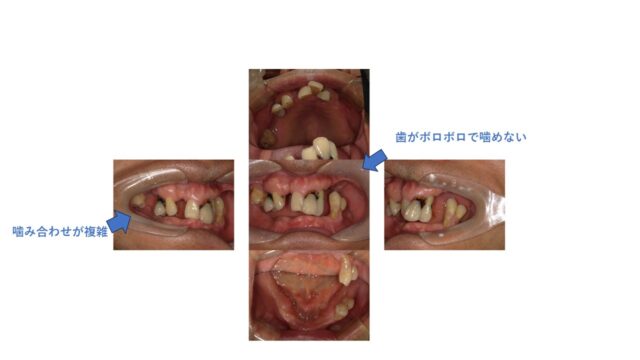

箕面市からお越しの72歳男性 歯がボロボロで食事がしにくい。インプラント治療希望で来院の患者様

| 症状 | 歯がボロボロで食事がしにくい。 |

| 年齢・性別 | 72歳・男性 |

| 治療期間 | 10か月 |

| 治療方法 | ・インプラント治療、歯周病 背景) 昔から歯が悪く、どんどんボロボロになってきた。かかりつけ医では骨がない・噛み合わせが 難しいので治療・インプラント治療を断られた。 治療方針) ①見た目を改善する。 ②食事のできる、噛み合わせの分析・考慮する ③①に対してインプラント治療を行い、噛み合わせ改善による早期の機能回復を行う。 上記内容を考慮して、 義歯治療とインプラント治療をおこなった。 患者様は今まで奥歯がなく、本来の噛み合わせがどこかわからない状態だった。まず、はじめに正しい歯の位置を分析した。 結果の正しい位置に対してインプラントを埋入した。 上は歯が残せそうなので自身の歯をつかってブリッジ治療にて回復、下は義歯とインプラントを併用したインプラント義歯とした。 患者様は審美面・機能面も満足され、硬いものでも噛めるとのことです。 |